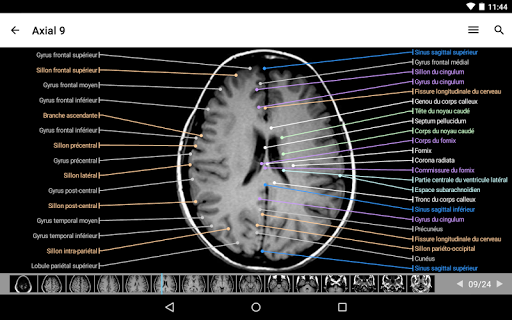

رسم توضيحي موجود الآن على كل صورة ويمثل الاتجاه الحالي للجسم

- عرض التشريحية يعرض الآن المزيد من التسميات

- وحدتان جديدتان: الدماغ - TOF والأوعية الدموية الدماغية ، أطلس التشريح الوعائي العصبي الطبيعي لشرايين الدماغ على الأوعية الدموية الدماغية. - تم إعادة صياغة الواجهة. - تتوفر علامة تبويب جديدة باسم "QuickLinks" ، ترسل وحدات في أقسام من جسم الإنسان وتسمح لك بالسفر السريع إلى الوحدات التي تبحث عنها. الخلل الصغيرة الثابتة.